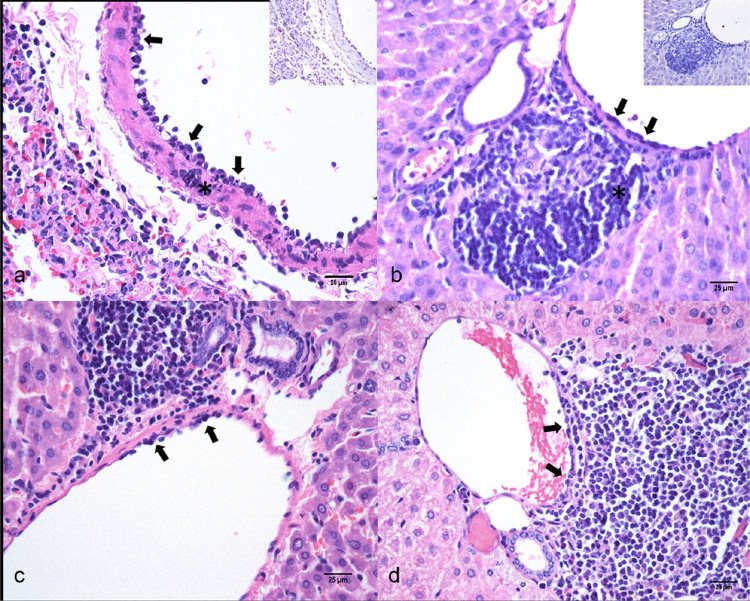

COVID-19 对肝脏的损伤尚未完全明了,在感染 SARS-CoV-2 的人类中,间接途径(肝脏中没有病毒复制)与激活肝脏损伤的血管机制有关。金色叙利亚仓鼠是实验再现 SARS-CoV-2 感染期间中度和自限性肺部疾病的有效模型。与在人类身上观察到的一样,这种实验模型可再现支气管间质性肺炎病变和肺血管病变,包括内皮细胞炎(淋巴细胞附着在内皮细胞的管腔表面)。在 COVID-19 中,肺外血管病变已被充分记录,但在 SARS-CoV-2 感染的金色叙利亚仓鼠模型中,这种肺外血管病变尚未被描述。本研究旨在评估实验性感染 SARS-CoV-2 的金色叙利亚仓鼠肝脏的显微病变。总共有 38 只常规金色叙利亚仓鼠,分为感染组(n=24)和模拟感染组(n=14),分别在感染 SARS-CoV-2 后 2、3、4、5、7、14 和 15 天安乐死。通过组织病理学和 SARS-CoV-2 Spike S2 抗原的免疫组化检测对肝脏碎片进行评估。在感染了SARS-CoV-2的动物中,门静脉内皮炎、肝小叶活动、肝细胞变性和肝小叶血管变化的频率较高。肝脏中未检测到 Spike S2 抗原。主要结果表明,SARS-CoV-2 感染加剧了原有不明原因肝炎仓鼠肝脏的血管和炎症病变。这种动物模型在研究与 SARS-CoV-2 感染相关的肝脏病变的发病机制和演变过程中的潜在应用仍需进一步评估。

Hepatic injuries in COVID-19 are not yet fully understood and indirect pathways (without viral replication in the liver) have been associated with the activation of vascular mechanisms of liver injury in humans infected with SARS-CoV-2. Golden Syrian hamsters are an effective model for experimental reproduction of moderate and self-limiting lung disease during SARS-CoV-2 infection. As observed in humans, this experimental model reproduces lesions of bronchointerstitial pneumonia and pulmonary vascular lesions, including endotheliitis (attachment of lymphoid cells to the luminal surface of endothelium). Extrapulmonary vascular lesions are well documented in COVID-19, but such extrapulmonary vascular lesions have not yet been described in the Golden Syrian hamster model of SARS-CoV-2 infection. The study aimed to evaluate microscopic liver lesions in Golden Syrian hamsters experimentally infected with SARS-CoV-2. In total, 38 conventional Golden Syrian hamsters, divided into infected group (n=24) and mock-infected group (n=14), were euthanized at 2-, 3-, 4-, 5-, 7-, 14-, and 15-days post infection with SARS-CoV-2. Liver fragments were evaluated by histopathology and immunohistochemical detection of SARS-CoV-2 Spike S2 antigens. The frequencies of portal vein endotheliitis, lobular activity, hepatocellular degeneration, and lobular vascular changes were higher among SARS-CoV-2-infected animals. Spike S2 antigen was not detected in liver. The main results indicate that SARS-CoV-2 infection exacerbated vascular and inflammatory lesions in the liver of hamsters with pre-existing hepatitis of unknown origin. A potential application of this animal model in studies of the pathogenesis and evolution of liver lesions associated with SARS-CoV-2 infection still needs further evaluation.